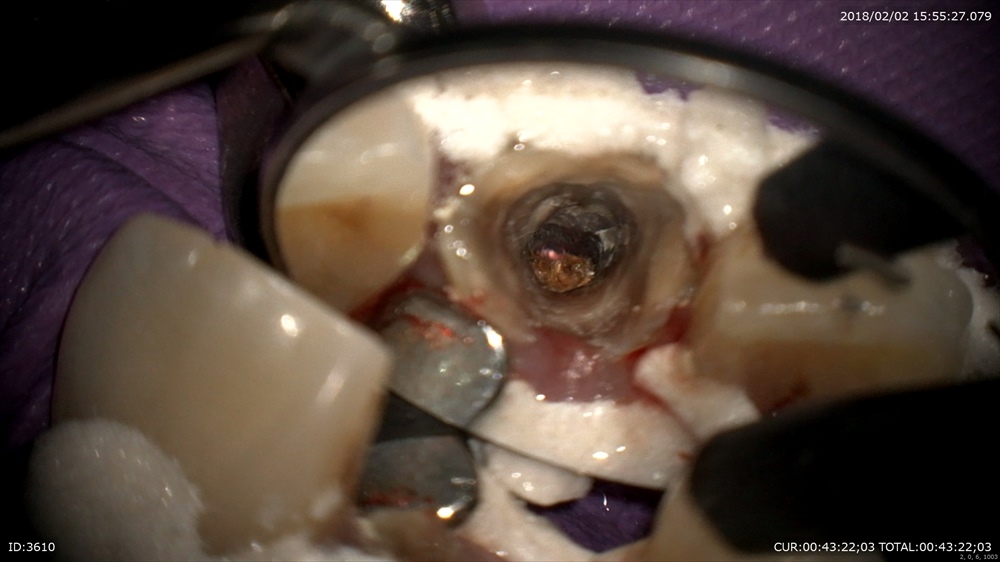

汚れ!ガッタパーチャが変色しています。

丁寧に感染を除去

レーザーをして綺麗に根管形成終了。

術前と術後

次回症状がなければ根管充填です。

2回で治療終了。